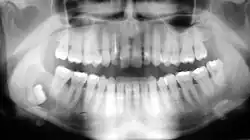

Bei größeren Zysten kann es zu Auftreibungen im Mundvorhof oder gar äußerlich im Kieferwinkelbereich kommen. Auf Druck kann man eventuell ein pergamentartiges Knistern wahrnehmen, wenn die oft dünne äußere Knochenlamelle zerbricht. Aufgrund ihres langsamen Wachstums, rufen odontogene Zysten lange Zeit keine Symptome hervor und treten so oft als „Nebenbefunde“ bei Röntgenaufnahmen auf. Zysten können auf Grund ihrer Verdrängung während ihres Wachstums Zähne verschieben oder kippen lassen. Es kann auch zu Wurzelresorptionen kommen, die wiederum zur Zahnlockerung (bis hin zum Zahnverlust) führen können.